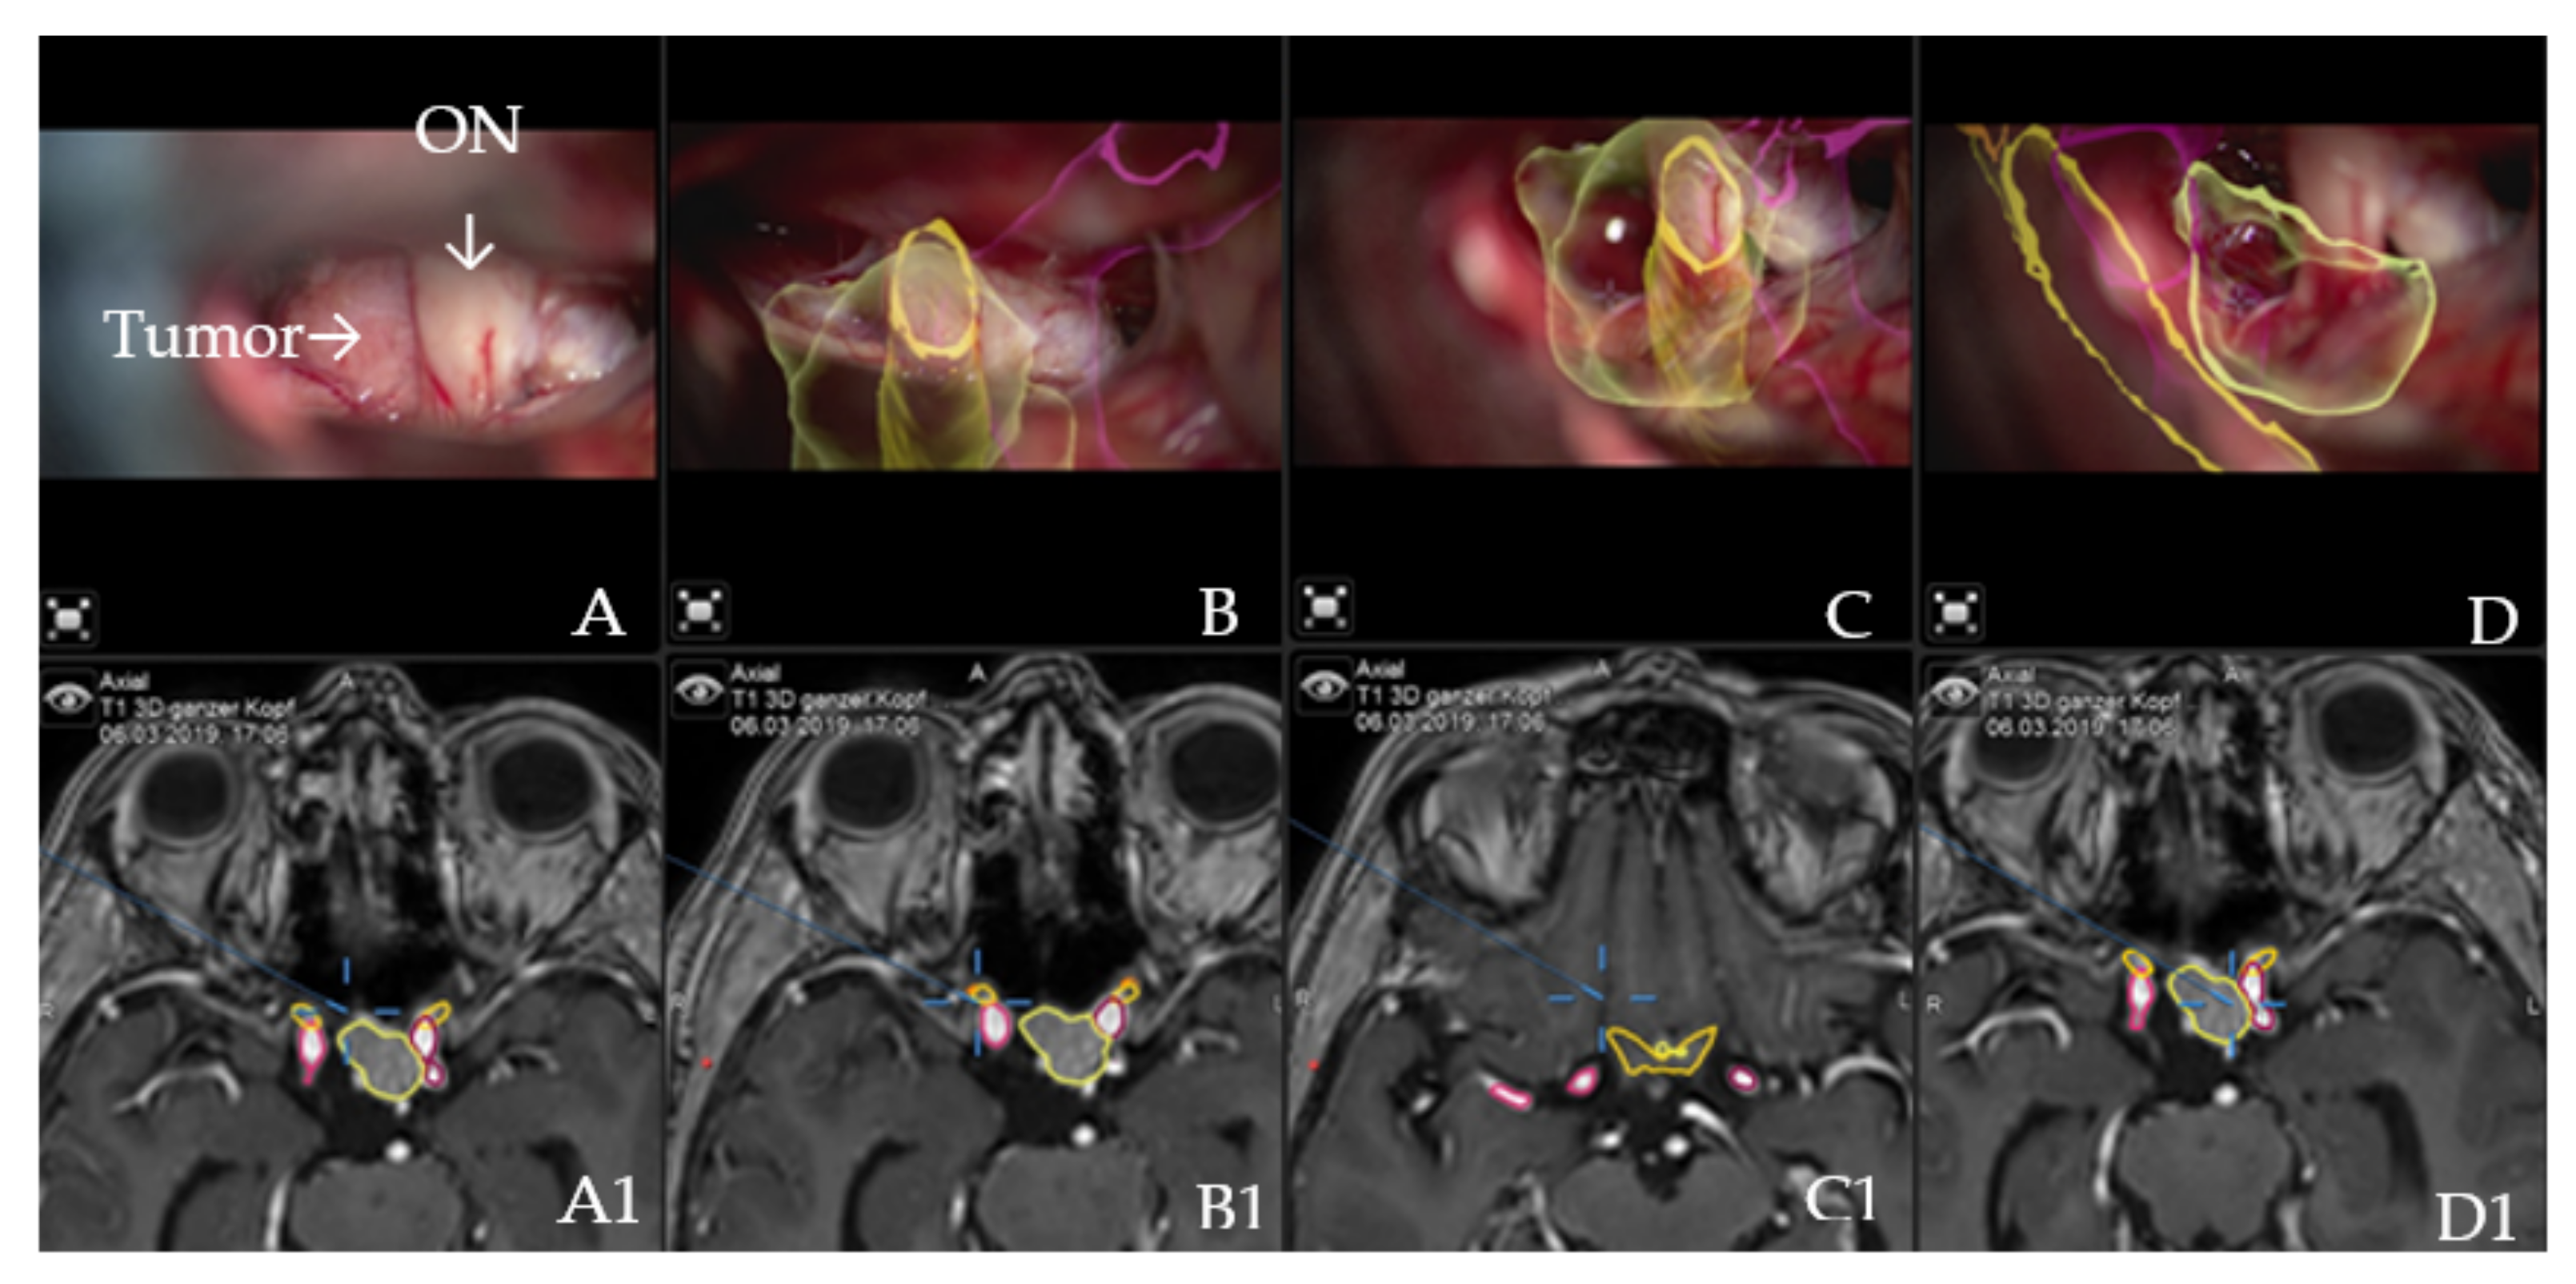

Figure 2. AR accuracy check. Patient no. 21 underwent a resection for suprasellar meningioma via right pterional approach. (A) Microscope video with focus on the tumor following exposure, with (A1) T1-weighted post-contrast MRI axial view of standard navigation display with segmented objects (tumor, optic chiasm and nerves in yellow and carotid arteries in violet). Focus of the microscope is shown as seen on the standard navigation display. (B) Microscope video with head-up display and 3-dimensional (3D) visualization of the segmented objects during the resection, with focus on right optic nerve, which shows high accuracy with the intraoperative situation. (B1) T1-weighted post-contrast MRI axial view of navigation, with focus on right optic nerve. (C) Microscope video with head-up display and 3D visualization of tumor outline, optic nerve and ipsilateral carotid artery following tumor resection with focus on the skull base with (C1) T1-weighted post-contrast MRI axial view of navigation. (D) Same as in C, microscope focus is on the contralateral carotid artery; segmented tumor outline and the course of the contralateral optic nerve are visualized with (D1) T1-weighted post-contrast MRI axial view of navigation, which shows focus of the microscope as seen on the standard navigation screen.

Augmented reality: The major indications to select a patient for surgery using the AR application were invasive tumors with encasement of the carotid and medial cerebral arteries, all tumors with close relation to the optic chiasm, giant tumors (tumor volume > 10 cm3) or recurrent tumors. Accuracy of patient registration and microscope registration were the two dependent variables for clinical AR accuracy. Microscope registration accuracy was checked by applying the AR visualization of the reference array outline. Landmark checks were successfully performed, apart from checking the target registration error (TRE), which confirmed high accuracy and excluded errors due to potential shift (Figure 2).

AR improved orientation in the surgical field for all patients as it reliably visualized the structures of interest and closely matched them to the visualized objects and the visible tumor outline. This was particularly useful in giant tumors with encasement and displacement of the cerebral arteries and compression of the optic chiasm (patients 4, 6, 8, 9, 10, 12, 13, 14, 18, 20, 22, 27, 31, 32, 33 and 36) as well as in cases of recurrent tumors (patients 24 and 35). No injuries to critical neurovascular structures occurred. The tumor was visualized in all patients, followed by vessels of interest (27 patients or 62.3%) and the optic chiasm and optic nerves in 22 patients, or 56.4%. Individual objects or HUDs could be switched off on the preference of the surgeon, in the case of AR information overflow. If this was the case, further AR support was provided by the standard navigation display and AR display on the video screens, which allowed the assisting staff to monitor the surgery, thereby serving as an educational tool.